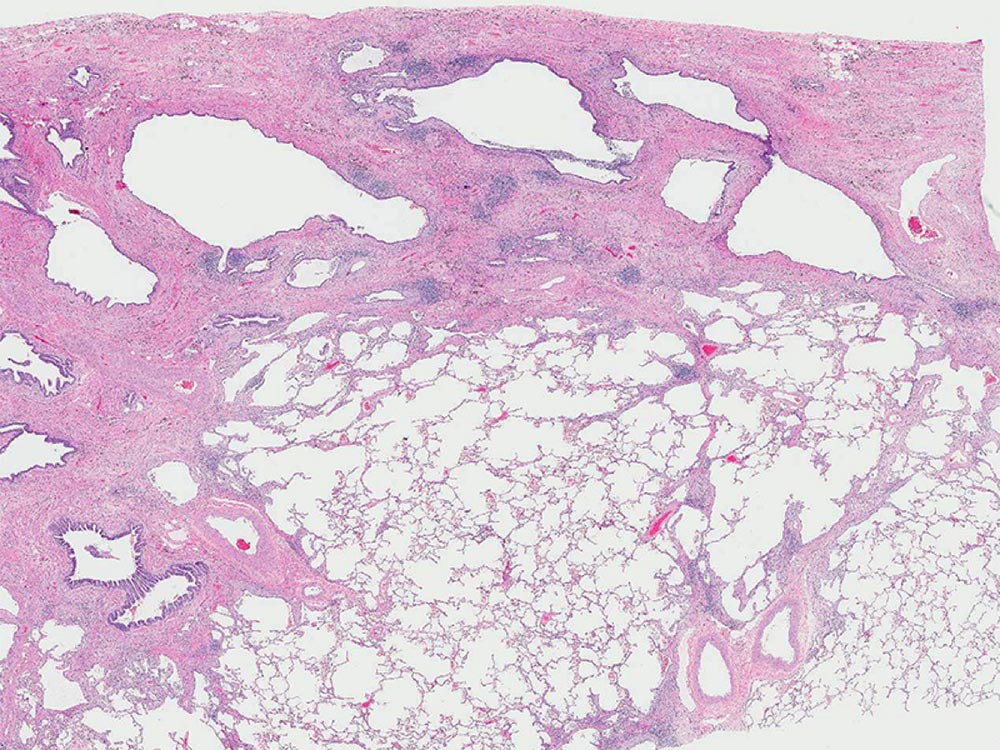

Low magnification photomicrograph showing the heterogeneous patchwork distribution of abnormalities classically seen with usual interstitial pneumonia (UIP). UIP appears as areas of fibrotic scarring with honeycomb change primarily affecting the subpleural and paraseptal parenchyma alternating with regions of normal lung tissue.

Image courtesy of and used with permission from Kirk Jones, MD.